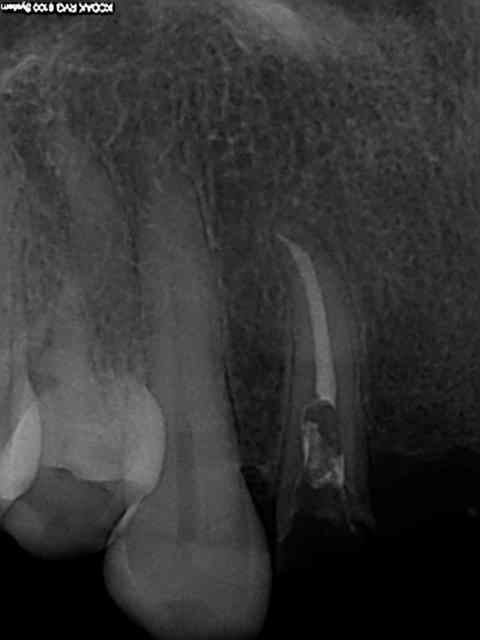

Bridge descellé, re-scellé plusieurs fois par plusieurs dentistes différents. la charte de bonne pratique est respectée (vu qu'on ne fait pas de prothèse) on re-scelle sur de la merde.

Bonjour l'odeur dans les canaux, Il fallait bien qu'il y en ai un qui y mette un terme.

Bien sur l'essentiel porte sur la ventilation des honoraires du bridge à refaire.

Je ne fais jamais de cathétérisme manuel, ca évite de casser des limes 15 de merde dans les canaux. d'ailleurs je ne sais pas ou elle est passée celle là, quelque part dans l'aspi je suppose.))))))

Reprise au R25 puis R40.

Charte de bonne pratique de merde, qui intéresse tout sauf la pratique. Ca m'énerve.